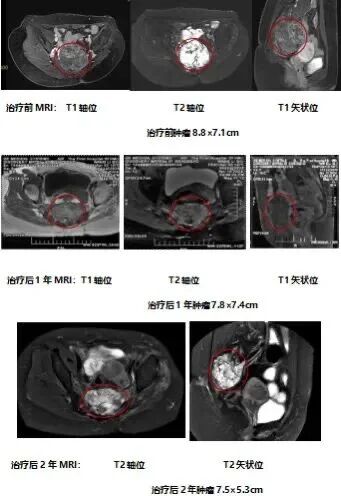

患者周先生的故事,正是这一技术价值的严峻注脚。他骶尾部生长着一个巨大脊索瘤,与直肠紧密粘连,常规治疗几乎无计可施。通过这项技术,外科医生术中巧妙置入隔离垫,为重离子射线开辟出安全走廊,最终对肿瘤实施根治剂量照射。术后,肿瘤得到显著控制,而紧邻的直肠安然无恙,完成了一次堪称完美的生命“拆弹”。